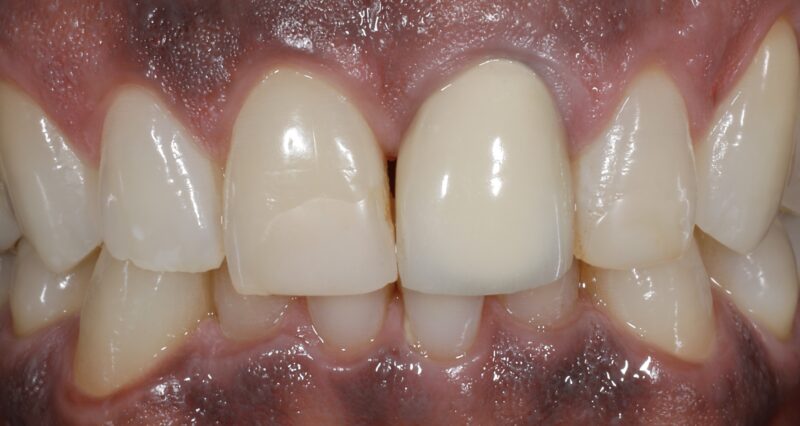

Simultaneous immediate implant placement and GBR (guided bone regeneration) utilizing CGF/PRF protocols on tooth #9 due to a failing root canal that destroyed the facial plate.

Reentry was between 5 and 6 months right after CBCT was taken and shortly after the site was restored. Upper right central incisor was crowned when the upper left…